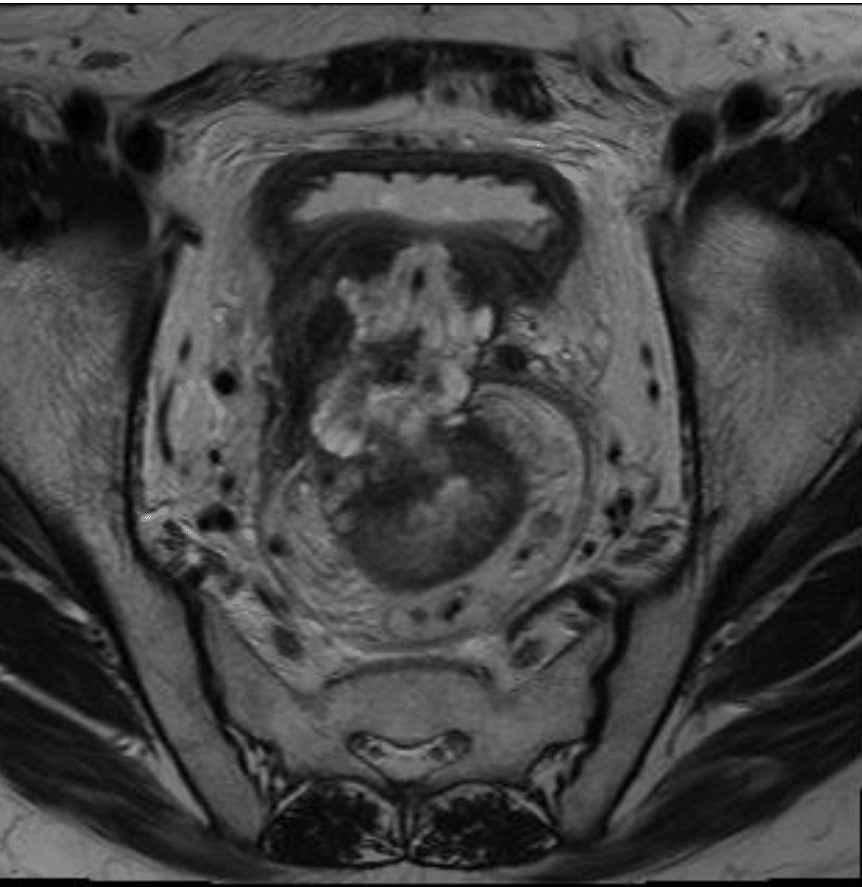

Management of Cystic Neoplasms of the Pancreas

- Updated guidelines for pancreatic cyst management have recently been released, including the 2018 European Consensus Guidelines, the 2017 American College of Radiology Guidance, and the 2016 Revisions to the International Consensus Guidelines.

- Epithelial histologic subtypes of intraductal papillary mucinous neoplasms have been shown to have important implications for prognosis.

- Pancreatic cyst fluid analysis for DNA biomarkers has shown promise for cyst diagnosis and detection of malignancy in the PANDA clinical trial and other studies although utility in clinical practice has not been demonstrated.

- A multidisciplinary team at Johns Hopkins Hospital published details of their multidisciplinary pancreatic cyst clinic outcomes, the first of its kind reported in the literature.